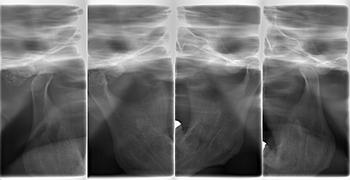

右側の顎関節部に塊状の不透過像が観察できます。

4分割撮影でも、下顎窩の所に塊状の不透過像が認められます。